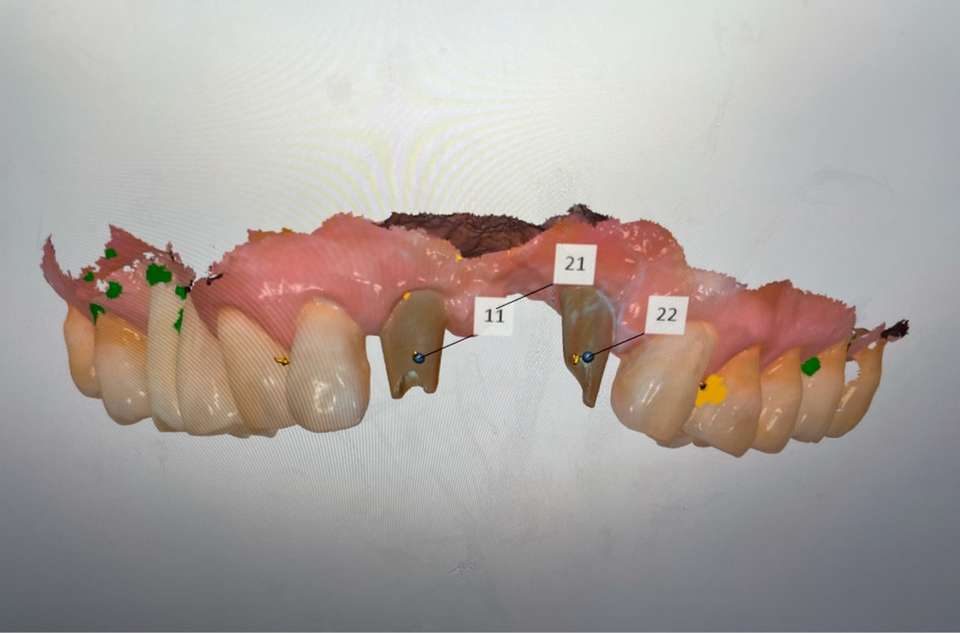

또한 internal 방식의 bone level과 tissue level의 external 방식 2종류로 구성되어 있고, 변환 abutment를 꽂으면 bone level이 tissue level로 변신한다. 그러면 디지털 보철 제작이 더욱 쉬운 형태로 바뀐다.

물론 개인적으로 3 piece 보다 2 piece가 나을 것 같기에 필자는 tissue level을 선호한다. 이렇게 internal을 external 방식으로 변환하는 이유는 디지털 스캔, Hexa 체결의 안착을 더욱 정확히 확인할 수 있기 때문이다.

또한 착탈이 가능한 스크류 방식의 보철로 제작하는데 fixture 식립각도의 차이에도 장착이 쉬운 외부 Hexa가 절대적으로 유리하기 때문이다. 또한 교합이 낮아지는 sink down 염려도 거의 없다.

보철 방식도 abutment (스크류 메탈 링크)를 스캔 바디로 사용하기에 디지털 소모품인 스캔바디비용이 들지 않는다.

보철 지대치로 스캔하기 때문에 항상 새 스캔 바디로 스캔하는 격이다.

구강스캐너로 스캔 시 정렬(매칭) 결과는 매우 만족스러웠다. 모델 제작없이 디지털로 상부 제작이 쉬운 이유이다.

세팅값을 조절하기 위해서는 구강 외에서 abutment를 스캔해서 자연치처럼 인식해서 제작해야 modelless로 작업이 가능하다.